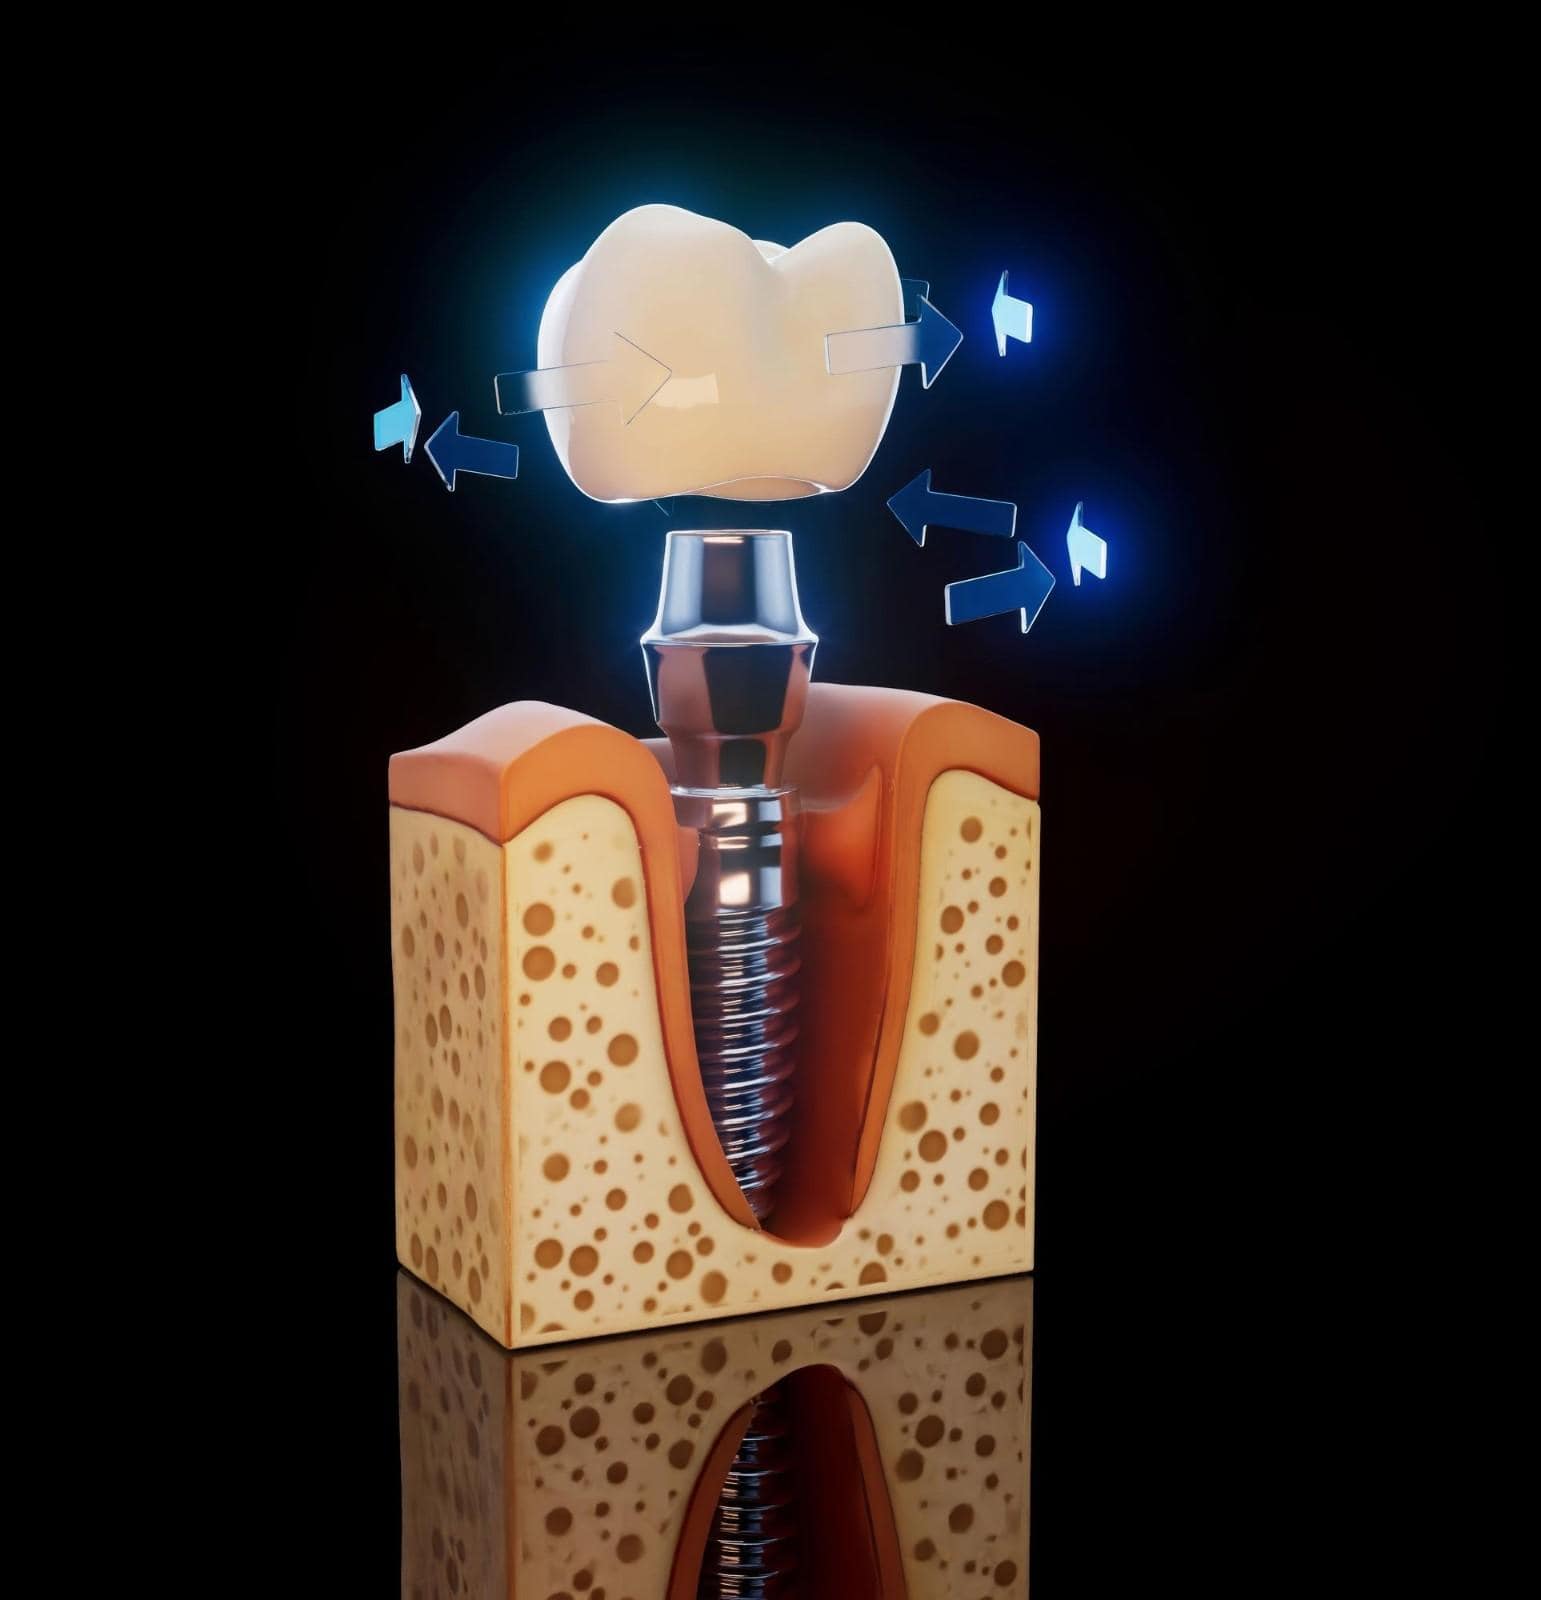

Gli impianti a carico immediato sono impianti dentali che ricevono una corona, un ponte o una protesi temporanea o permanente lo stesso giorno del posizionamento dell'impianto. Questa tecnica avanzata consente ai pazienti di lasciare la clinica con denti funzionali immediatamente, senza aspettare mesi per la guarigione tradizionale dell'impianto.

Per eseguire il carico immediato in modo sicuro, l'impianto deve raggiungere una forte stabilità primaria ed essere supportato da un'adeguata densità ossea. I dentisti misurano attentamente la stabilità dell'impianto per garantire che possa sopportare le normali forze masticatorie fin dall'inizio.

Chirurgia di Posizionamento dell'Impianto

Gli impianti dentali vengono posizionati nell'osso mascellare seguendo il piano digitale. Durante l'intervento chirurgico, il dentista monitora attentamente il posizionamento dell'impianto e la risposta ossea. La stabilità dell'impianto viene controllata immediatamente dopo il posizionamento.

Verifica della Stabilità dell'Impianto

Ogni impianto viene testato per confermare che abbia una stabilità primaria sufficiente per supportare il carico immediato. Solo gli impianti che soddisfano rigorosi requisiti di stabilità procedono con il ripristino nello stesso giorno. Questo passaggio garantisce sicurezza e successo a lungo termine.